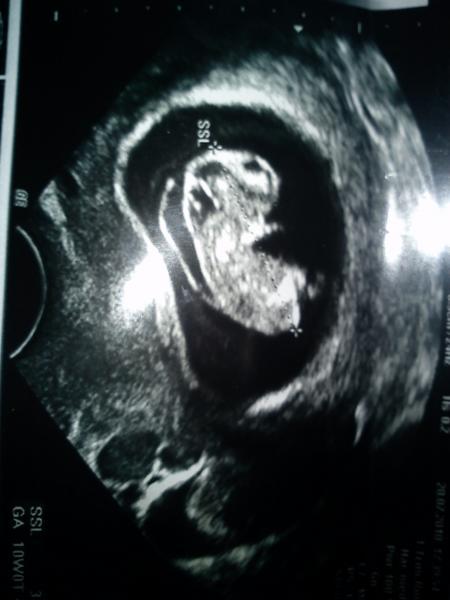

ein guter arzt mit einem guten gerät kann durchaus auffälligkeiten im ultraschall feststellen. aber auch ein vorhandenes nasenbein oder eine nackenfalte im normbereich geben dir keine garantie. die freundin meiner schwester hat mit glaube ich 27/28 jahren ein mädchen mit down syndrom bekommen. sie hatte die 3 normalen us untersuchungen, nackenfalte lag bei 1,1 mm. sie hatte aber keine feindiagnostik. eventuell wäre etwas aufgefallen oder auch nicht. die kleine maus hatte bei der geburt ein leichteres gewicht, war aber wohl normal groß. uns gab man allerlei horrordiagnosen und unsere ultraschalls waren bei beiden kindern mehr als auffällig (zumindest immer die nackenfalte). nummer 1 ist putzemunter und gesund und schon 2 1/4 jahre alt. nummer 2 schlüpft im februar, hatte ein hygroma colli und eine nackentransparenz von 4,10 mm und ist genetisch gesund. lg claudia & ben & mausi inside ps.: anbei die diagnose :-) (jetzt kann ich darüber lächeln).

Bild zu